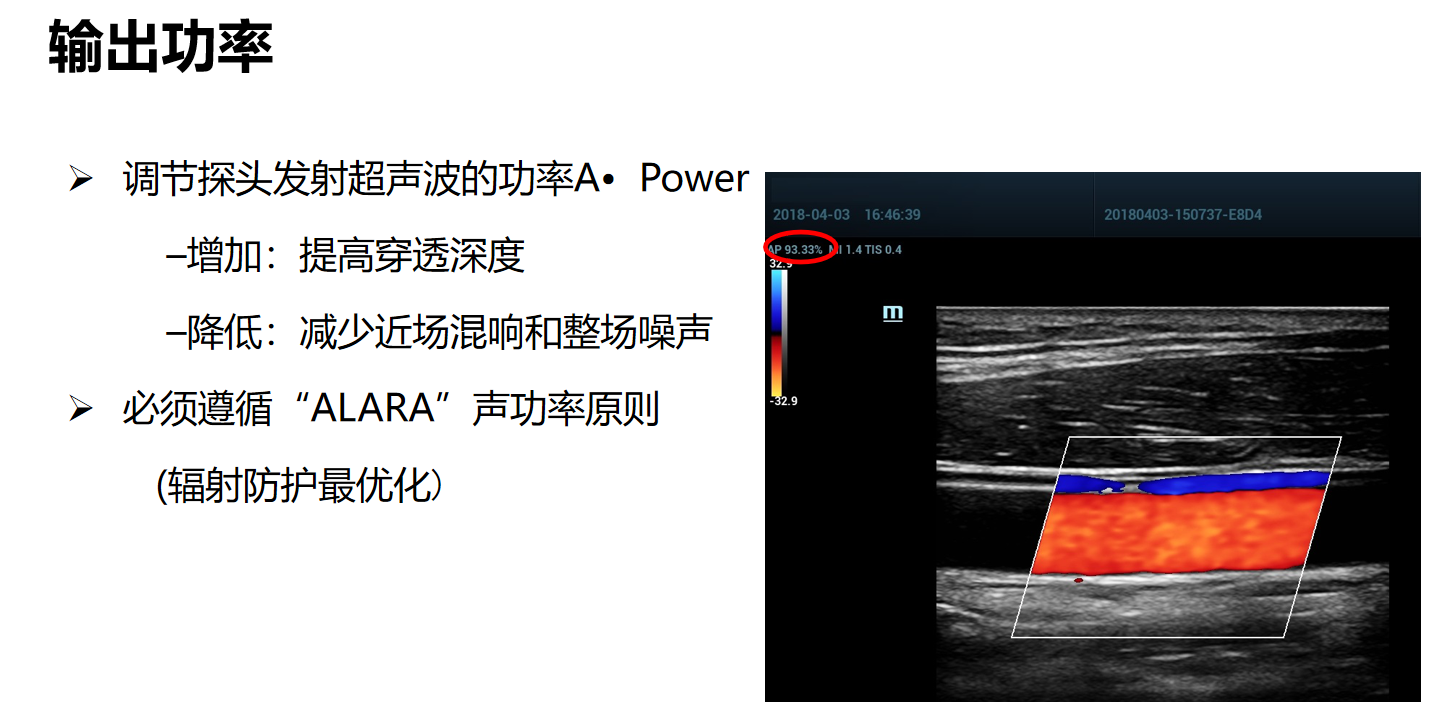

输出功率是探头发射超声波的功率,声功率(AP)值实时显示于屏幕左上方。

参数可调节范围:0.1%-100%。增大声功率,图像整体亮度均匀增加,探测深度也增加。声功率减小,穿透力减弱。在临床应用时必须遵循“辐射防护最优化原则,根据实际情况选择适当的声功率。